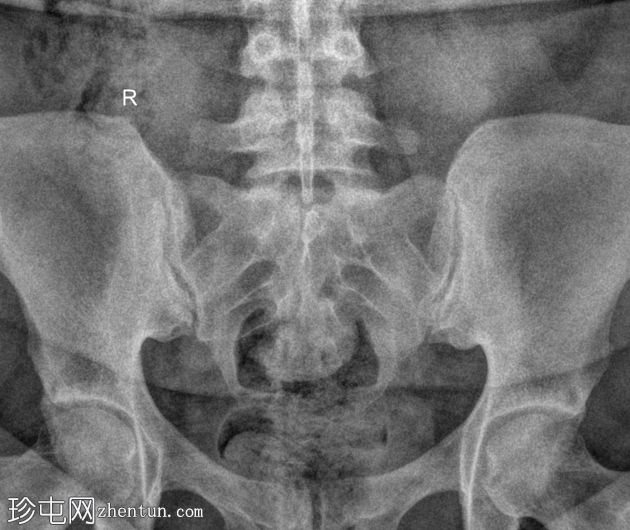

斜位

骶髂关节正位和斜位X线片显示正常。